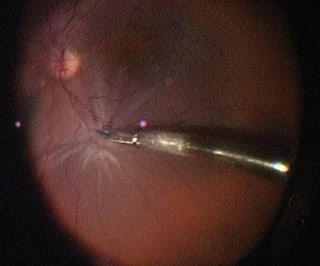

Some ERMs are subtle and difficult to visualize, yet they may be clearly seen on optical coherence tomography scanning and may be symptomatic in select patients. Intraoperatively, the ERM may be difficult to visualize and it may not be possible to identify an edge. This can lead to incomplete peeling or, in some cases, no peeling, if the ERM cannot be identified. Inability to remove the ERM or excessive retinal trauma are undesirable in a patient with a symptomatic 20/30 ERM. Staining with Membrane Blue solves this problem, allowing safe and complete ERM removal (Figure 1).

IMAGES COURTESY OF BRIAN C. JOONDEPH, MD, FACS

Figure 1. Partially peeled epiretinal membrane stained with Membrane Blue.